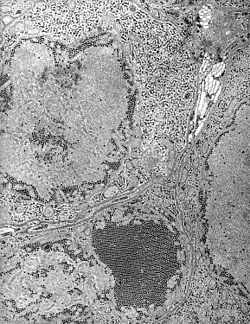

![]() Sección de las gándulas salivares de un mosquito conteniendo las partículas del virus. | ||